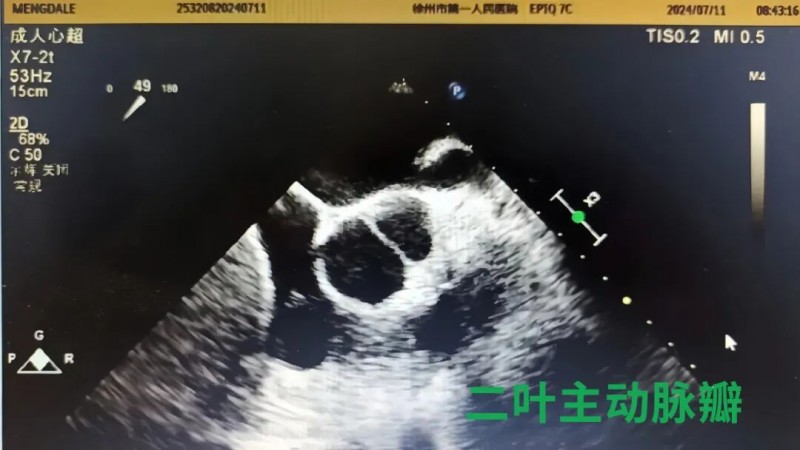

经食管超声心动图,英文简称TEE,就是将超声探头置入食管内,从心脏的后方向前近距离探查其深部结构。它与普通的经胸超声心动图(TTE)检查相比,避免了肥胖、肺气肿、胸廓畸形等的影响,故可显示出清晰的图像;另外,TEE的探头频率较高,分辨率也更高,因此对组织结构分辨力更强,超声图像更清晰,大大提高对心血管疾病诊断的敏感性和可靠性,便于进行心脏手术中的超声监测与评价。

目前,徐州市第一人民医院超声医学科已成功开展了近百例经食管超声心动图检查,进一步提高了心脏疾病诊断的敏感性和可靠性。这项新技术为心脏超声检查开启了另一扇“声窗”,填补了院内空白。